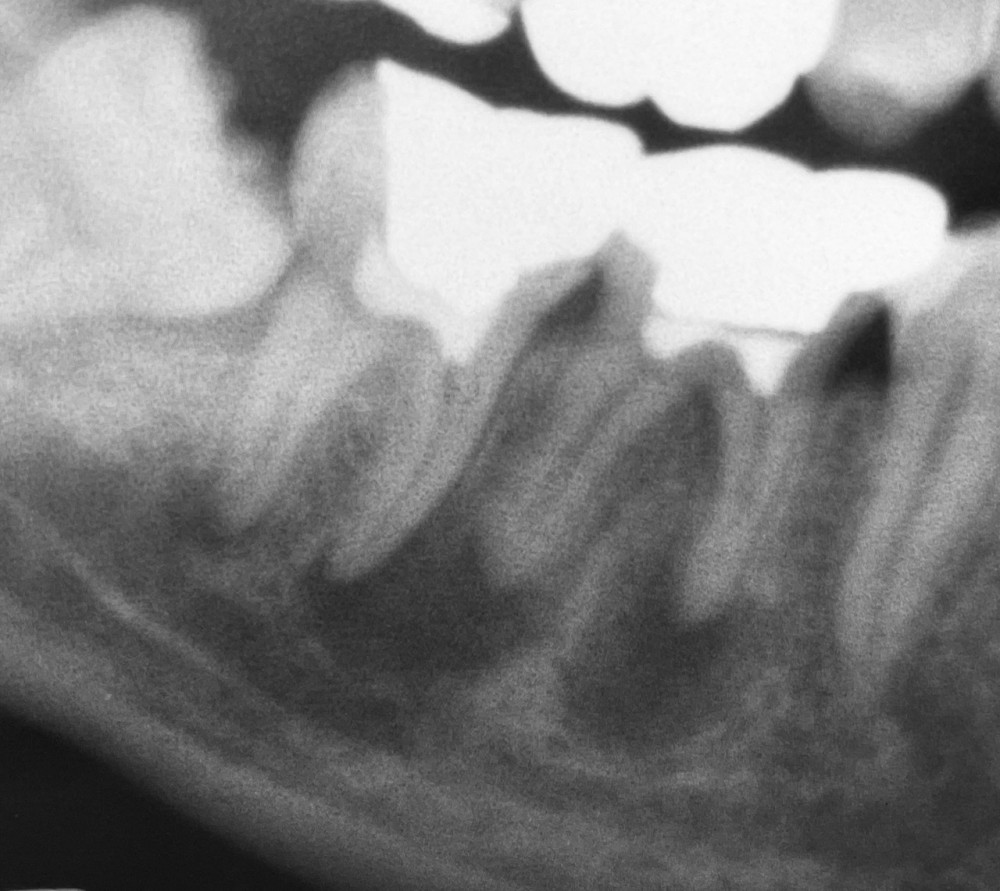

わかりやすく見ていただくために、術前と半年後のエックス線写真2枚を並べてみます。

令和4年12月撮影

令和5年6月撮影(半年後)